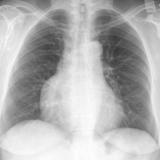

Case 1 PA

Peric calcification

Date: 03/17/2004

Views: 2585